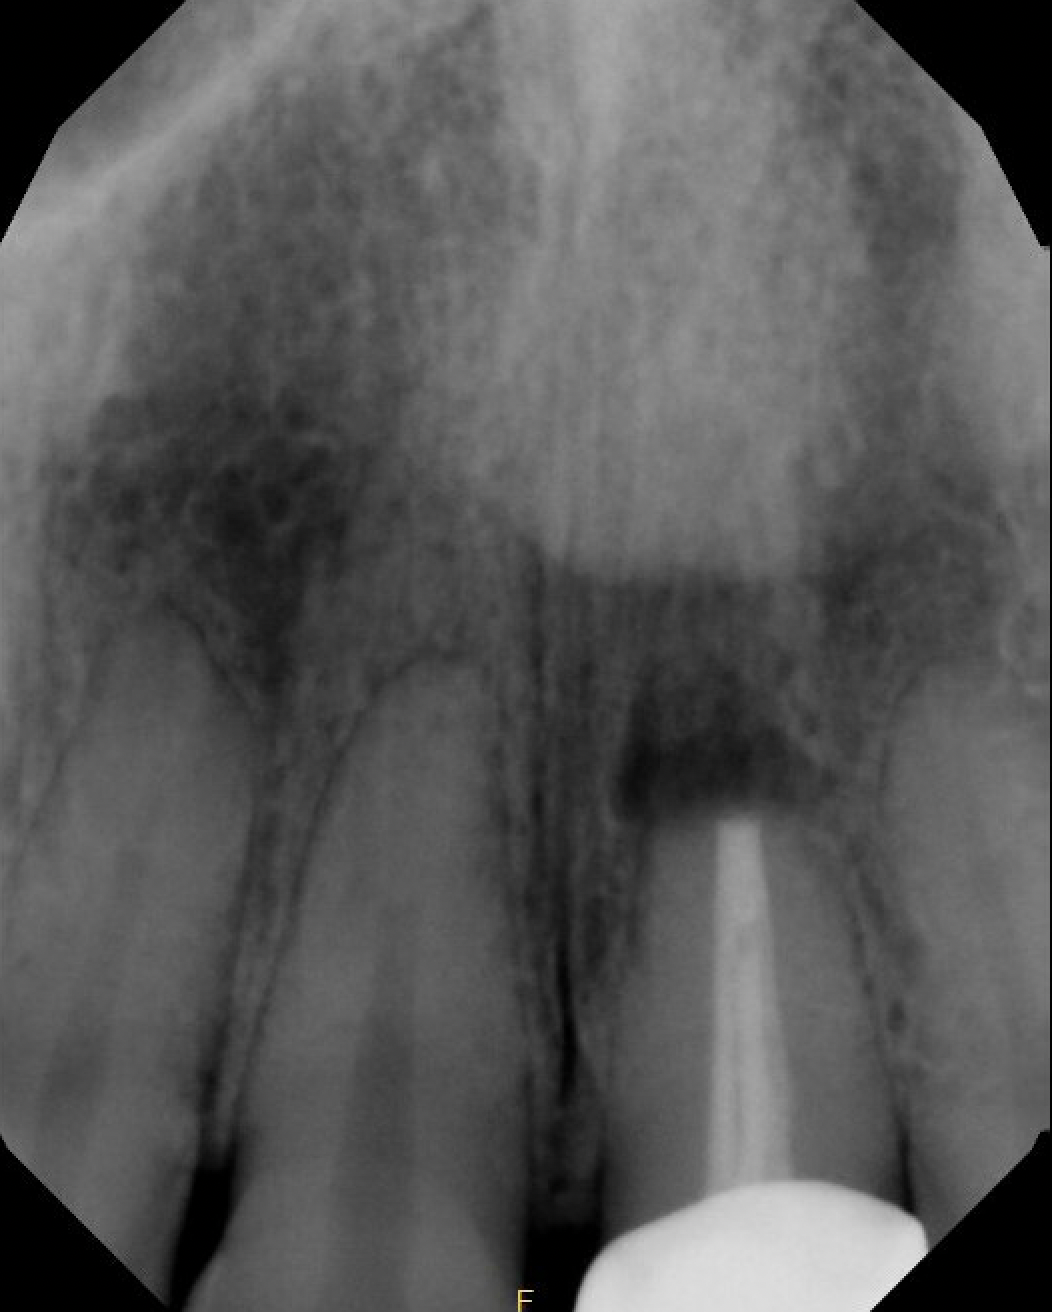

#10 S-RCT